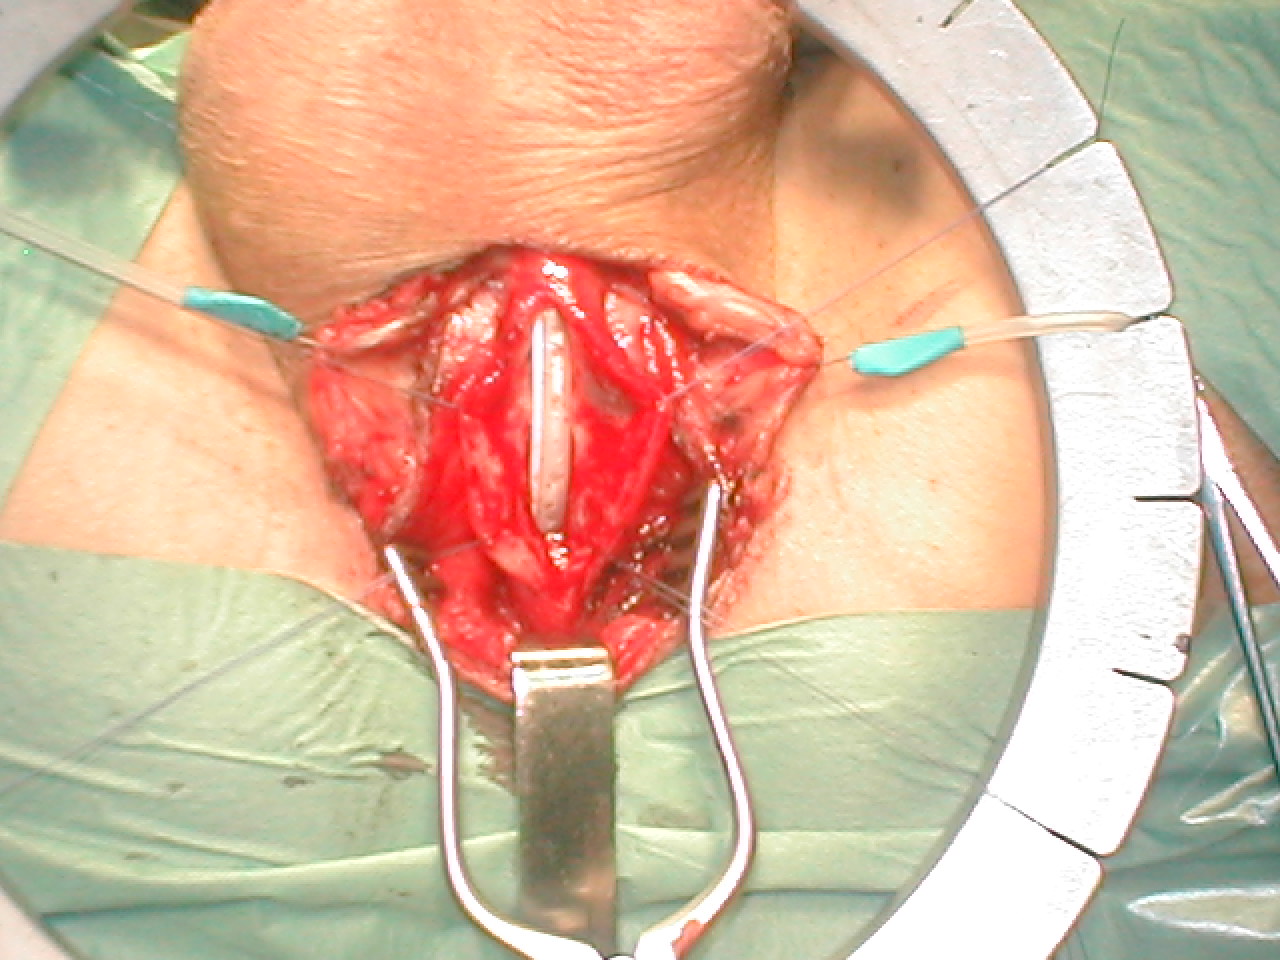

Буккальная 1 этапная уретропластика – Фотогалерея